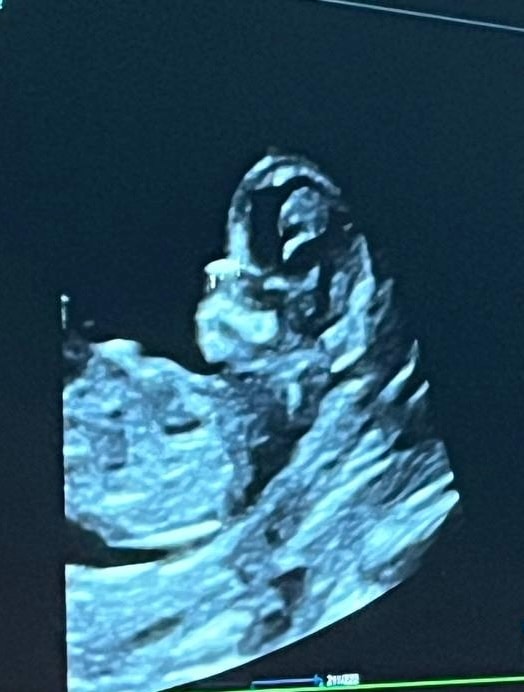

1 скрининг

Пол малышаТак надеялись хотя бы предположительно узнать пол, а врач сказала, что непонятно 🙃Может быть есть люди тут с пониманием, кто разбирается в наклоне полового бугорка и может подсказать 🥲 А где-то вычитала, что даже по форме черепа смотрят 😅